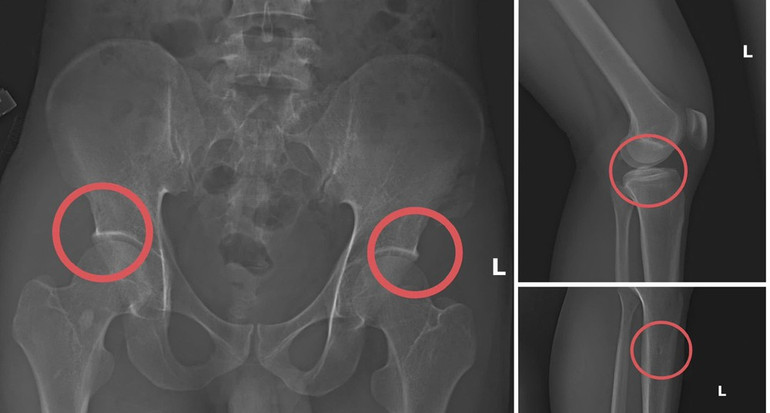

Примітно, що Чау безпосередньо вводив анестетик та використовував шприц і молоток, щоб вдарити по кістках страхового покупця, створюючи переломи, схожі на справжні нещасні випадки. Після того, як травми були створені, Чау продовжував інструктувати суб'єктів створювати фальшиві сцени, такі як ураження електричним струмом, падіння або ковзання та падіння у струмок, щоб легітимізувати медичні записи та заповнити файл запиту на оплату.